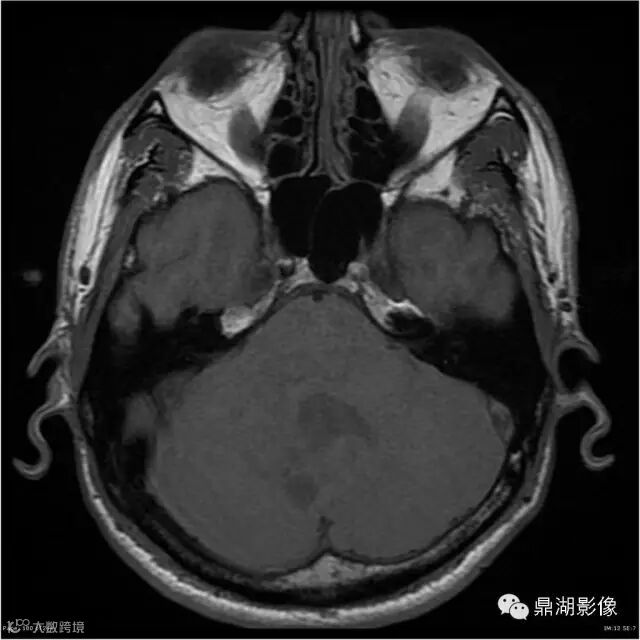

患者男,53岁,头痛、视乳头水肿伴双下肢无力。

影像:可见一个约43 x 36 x 31mm的从小脑蚓部延伸而来的占位,T1WI、T2WI呈高低混杂信号,病灶周边见流空血管影及水肿带,增强病灶明显强化,中心见无明显坏死区,它紧靠左小脑幕上。第四脑室受压变窄,室管膜水肿,可见脑桥及延脑扁桃体进入枕骨大孔。

本例为一例实质性血管母细胞瘤。实性血管母细胞瘤CT平扫示病灶呈等或高密度,增强后可见明显强化。MRI平扫通常病灶很不均质,T1呈稍低信号为主的较混杂信号,T2呈等、高信号,DWI通常呈低信号或等信号。文献报道,实性血管母细胞瘤较典型的表现为瘤内及瘤周扩张的流空血管影,瘤周中、重度水肿。因此,小脑半球区的单发肿块伴流空血管影,周围大片水肿以及增强后肿块明显强化"形态规则"边界清楚,此时应将实性血管母细胞瘤考虑在内。